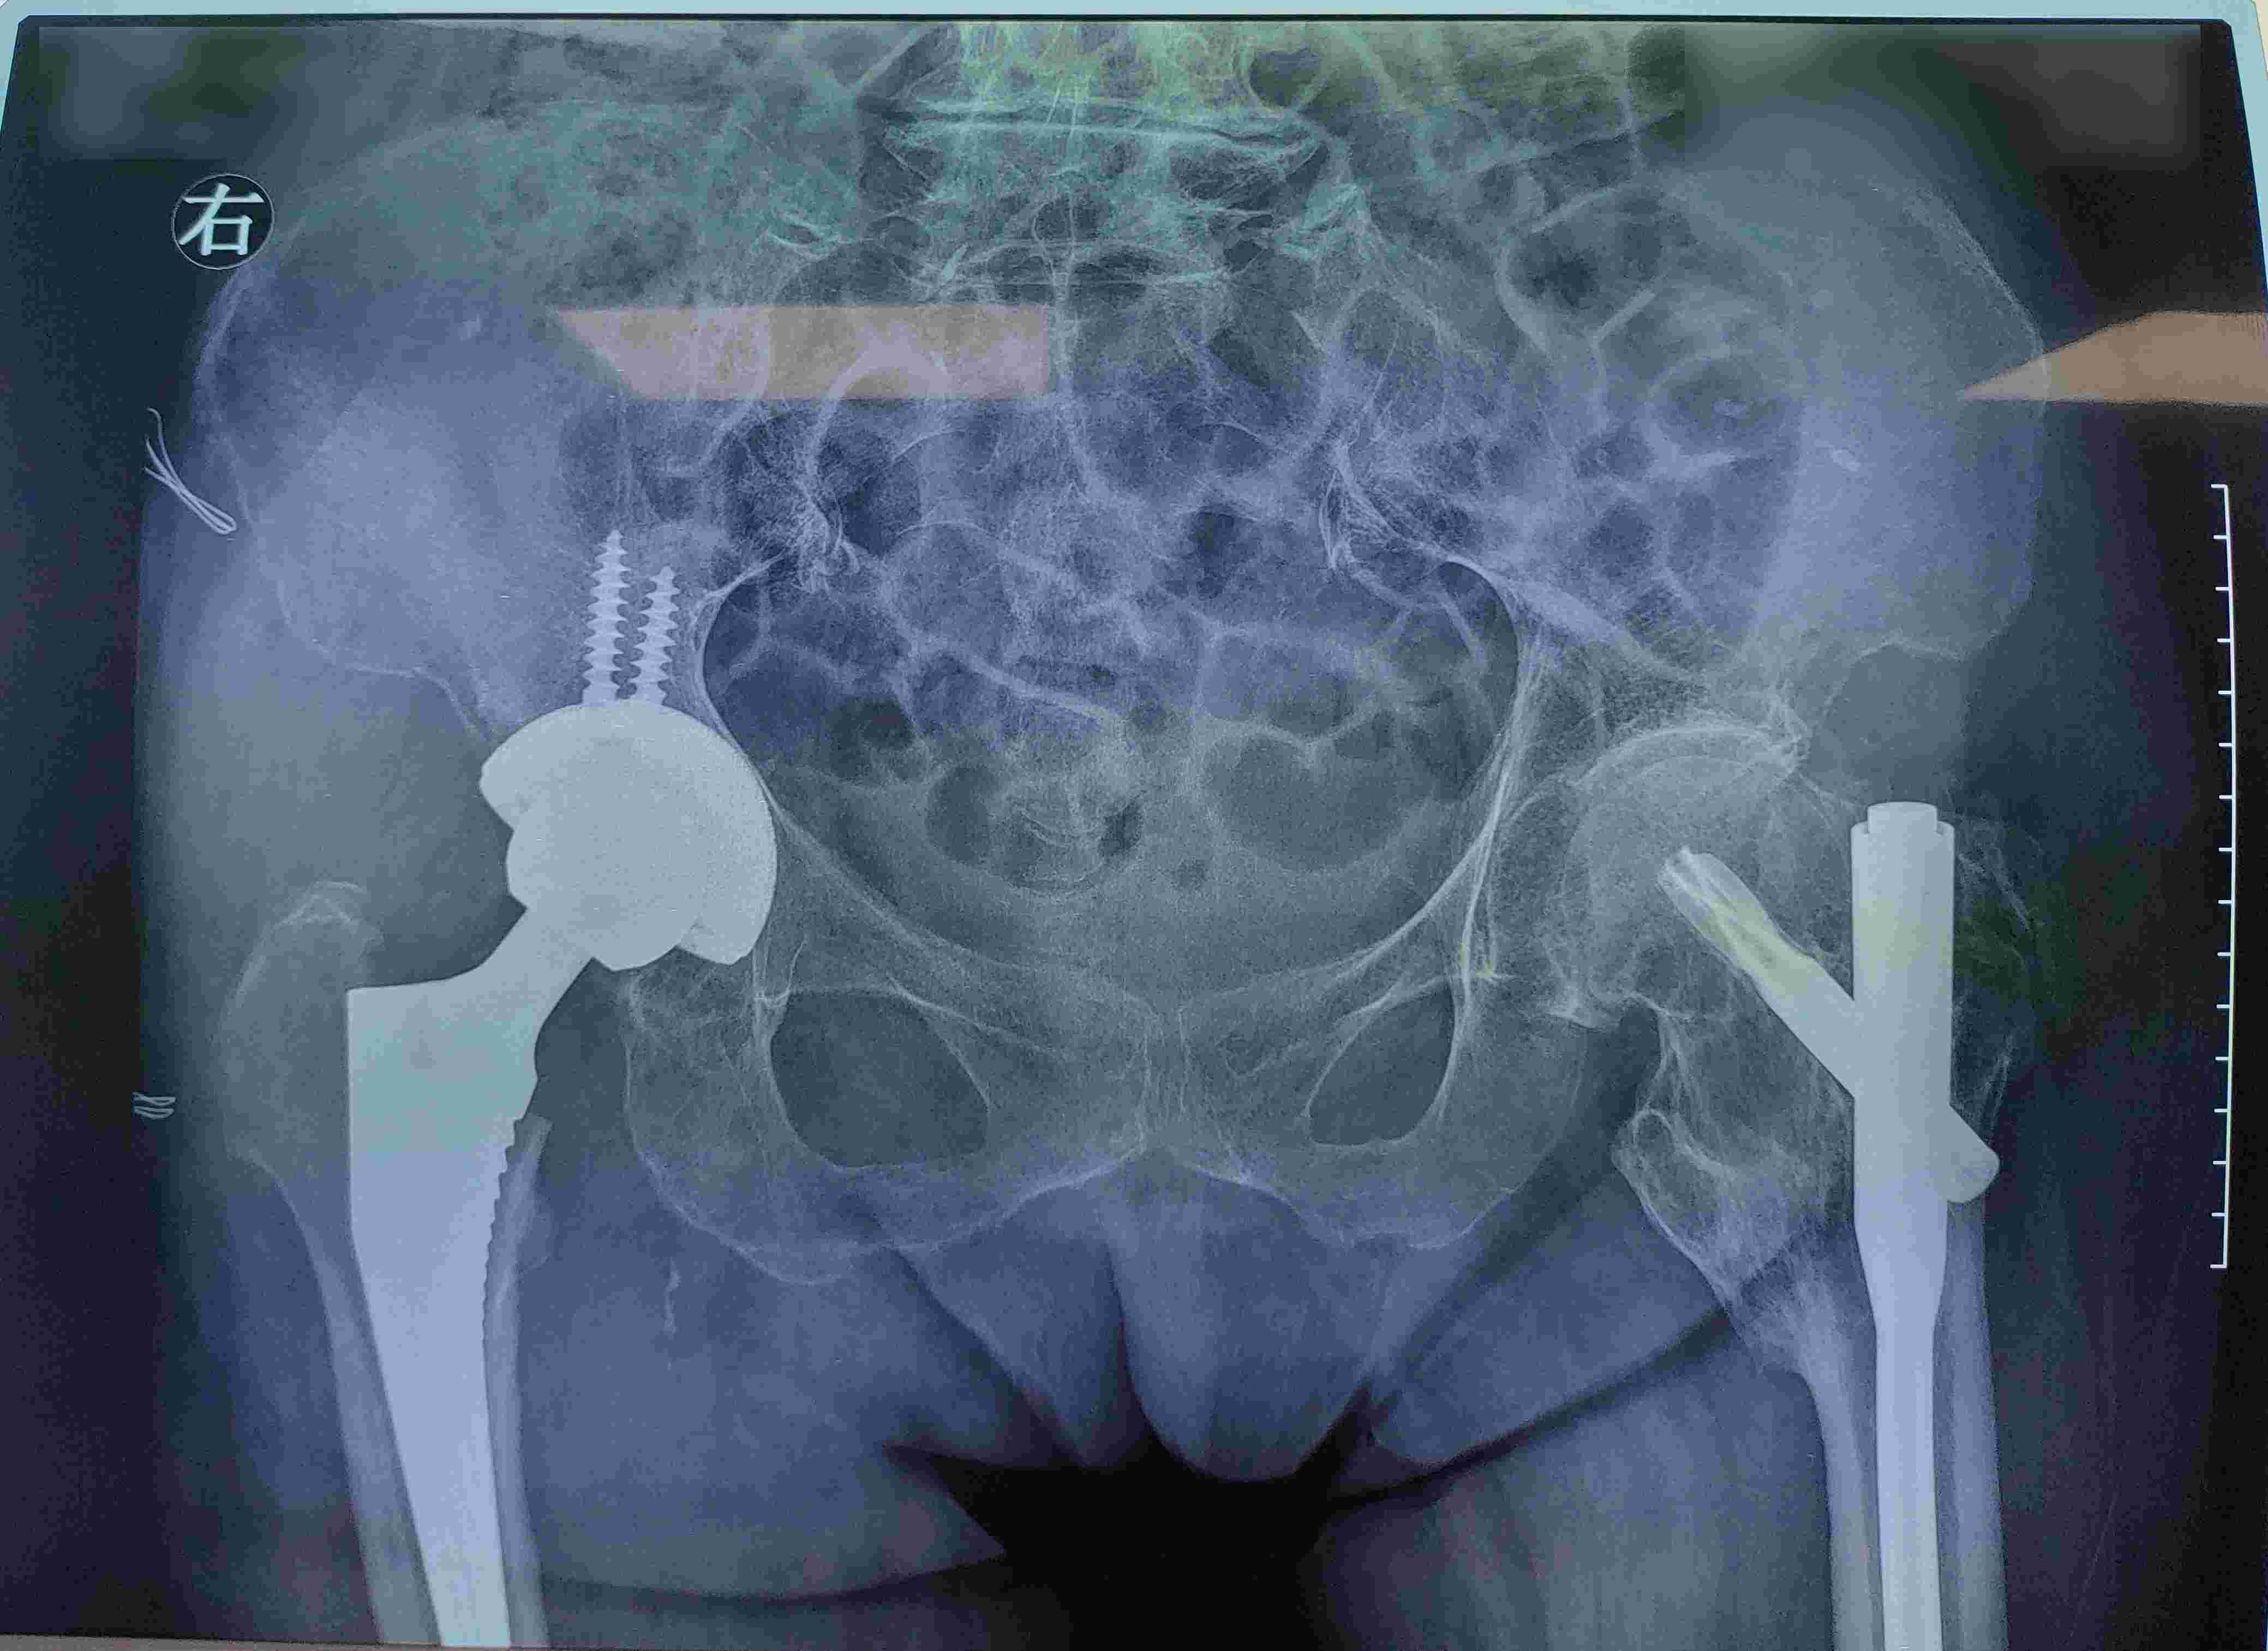

术后

马文龙联合我院援疆专家李保华、宋懿泽,与哈密市维吾尔医医院团队制定了个性化手术方案。在大家通力合作下,手术历时两小时顺利结束。术后几日,患者恢复良好,复查时,患者向我院援疆专家与哈密市维吾尔医医院团队表达了深切的感谢。